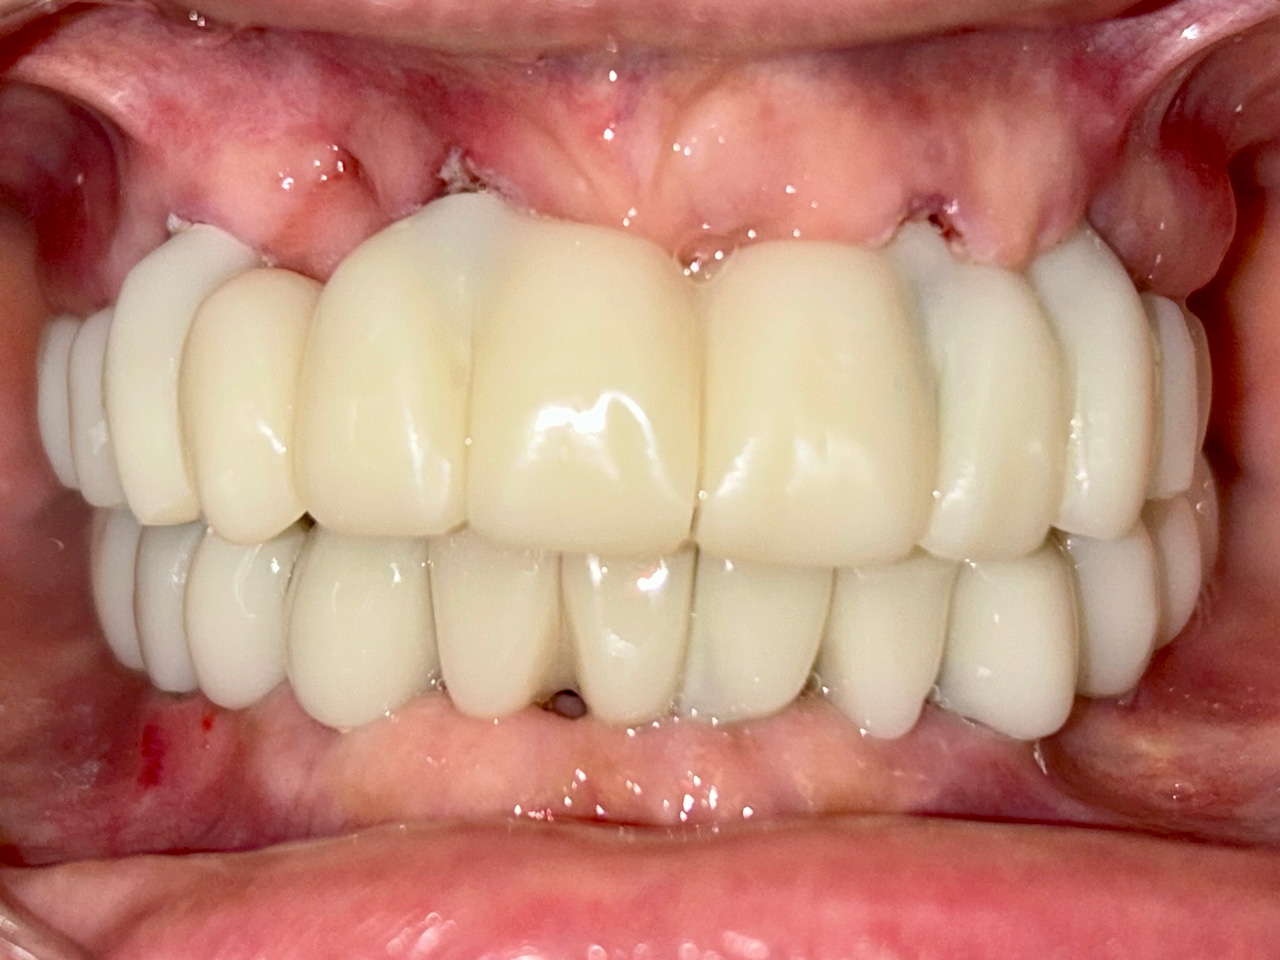

Teljes fogatlanság helyreállítása 2 nap alatt

Teljes fogatlanság helyreállítása 2 nap alatt azonnal terhelhető svájci IHDE implantátumokkal és PMMA műanyag hidakkal. Intraorális szkennerrel vettünk lenyomatot az implantáció után, és erre a digitális mintára készítette el a fogtechnika a hidak digitális tervezését, majd faragta ki műanyagból. Ezt a gyors munkát az azonnal terhelhető implantátumok és a digitális lenyomat, tervezés segítségével tudtuk megcsinálni mindössze 2 nap alatt. Dr. Kelemen Péter és a Symbion Fogtechnika munkája.